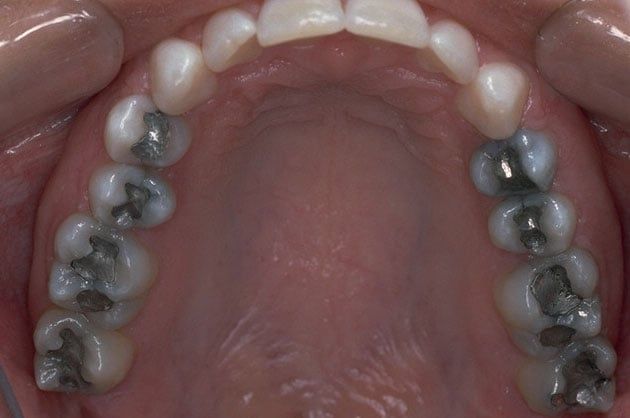

Composite fillings are today's modern filling choice. They are made to match your tooth's natural color to make them virtually invisible to notice and are placed onto the tooth by bonding the filling material to the tooth so they do not have the unlikely chance of falling off. Many patients choose to replace their old silver and gold fillings with composite fillings.

White fillings are made from a high-strength composite resin that can be easily color-matched to your natural tooth making it nearly invisible to you and anyone else. Unlike silver and gold fillings, composite tooth-colored fillings actually bond to the tooth which means they support the surrounding tooth structure, which helps to prevent breakage and insulate the tooth from excessive temperature changes. You are much less likely to have a composite filling fall out which is a common issue with metal fillings.